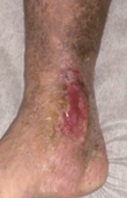

潰瘍(かいよう)

下肢静脈瘤による潰瘍で足を切断しなくてはならないことはありませんが、細菌が入って感染を引き起こしたり、痛みや出血などで日常生活にかなり支障をきたしてしまいます。